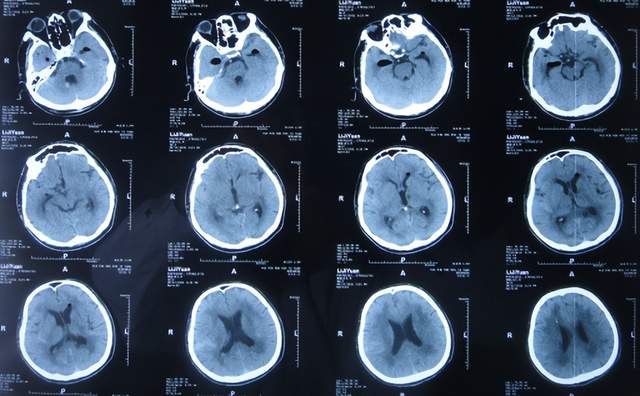

患者于2021年9月2日突发昏迷,急送至当地的山东省滨州市惠民县某医院,查头颅CT示脑出血破入脑室(图-1),急诊行双侧脑室外引流术;脑出血后血压偏低,给予输注入人血白蛋白。

图-1:2021年9月2日头颅CT

术后次日即2021年9月3日,患者意识转清醒,能简单言语,肢体可以遵嘱抬起;查头颅CT示双侧脑室引流术后,脑室积血(图-2)。

图-2:2021年9月3日头颅CT

双侧脑室外引流术后3天即2021年9月5日,查头颅CT示脑室内积血减少(图-3)。

图-3:2021年9月5日头颅CT

双侧脑室外引流术后6天即2021年9月8日,再次查头颅CT示仍有少量积血(图-4);给予常规拔除了双侧脑室外引流管,同时进行了腰大池引流术。

图-4:2021年9月8日头颅CT